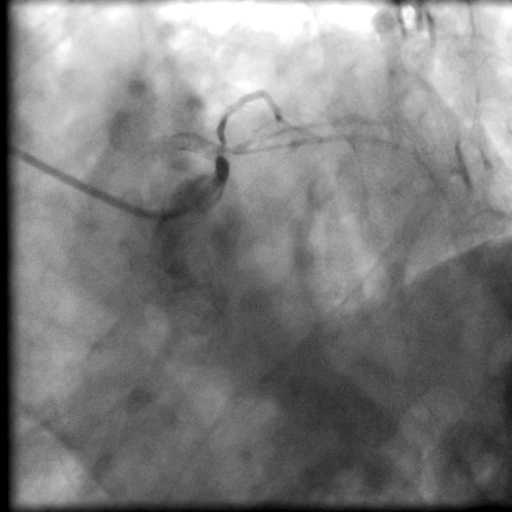

Angiogram showed satisfactory result overleft main/ramus/circumflex from prior drug coated balloon. LAD was totallyoccluded right from the ostium with an ambiguous proximal cap. Fortunately thecourse of the vessel was highlighted by the presence of calcium and stent, butthe CTO length was long. Bilateral dual injection showed faint retrograde fromright coronary artery only. J-CTO score was 3.

Bilateral injection.avi